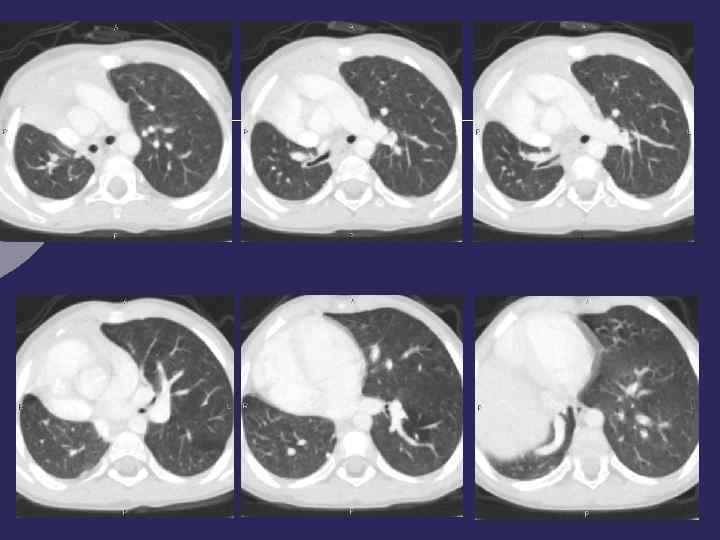

Врожденные неосложненные кисты

Врожденная бронхоальвеолярная киста (с обычным кровоснабжением) - Ø нарушение развития на уровне бронхо- альвеолярного ветвления, в капсуле - элементы бронхиальной или альвеолярной стенки Ø Одиночная или множественные Ø Бессимптомно до момента нагноения, затем - клиника рецидивирующего воспаления Ø Осложенные, неосложненные Ø Локализация – 2/3 случаев верхняя доля левого легкого

Неосложненная киста Ø Правильная округлая или овальная форма Ø Легочная ткань вокруг не изменена или рисунок слегка деформирован Ø Структура однородная Ø Визуально - плотность высокая, денситометрическая плотность соответствует жидкости Ø После опорожнения – воздушная полость с тонкой, равномерной стенкой Ø М. б. горизонтальный уровень жидкости Ø При бронхографии – чаще не контрастируется, бронхи раздвинуты

Врожденная воздушная киста • Дренирующий бронх не виден • Бронхи огибают кисту